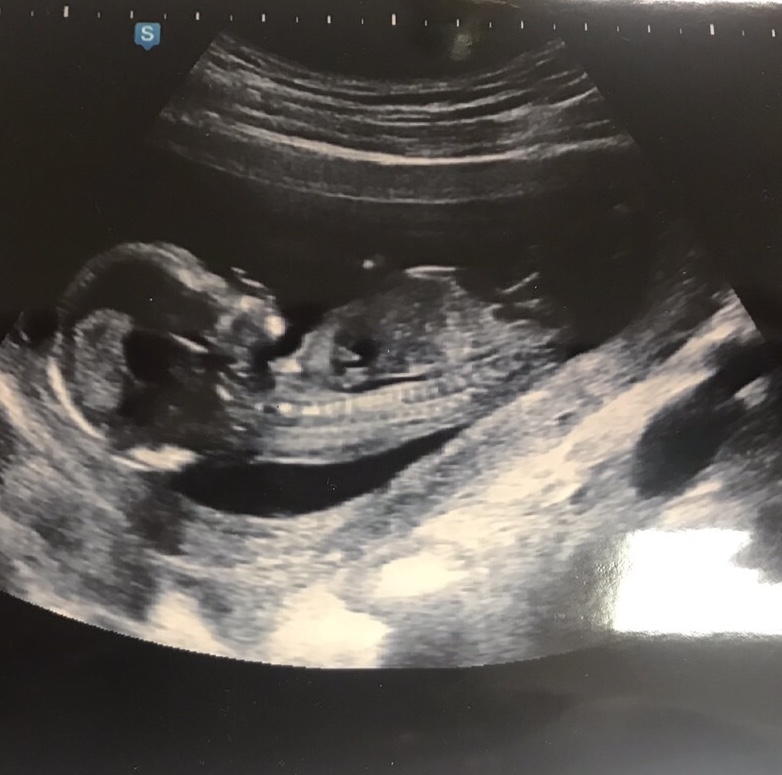

Je to holčička nebo chlapeček? Foto ultrazvuku

Přikládám foto ultrazvuku holčičky v 16tt pro ostatní maminky pro porovnani, je to zaber zespodu jakoby na prdku s roztazenyma nozkama 😉.